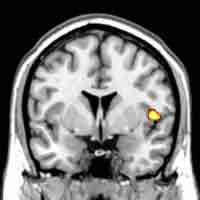

MRI brain scan highlights the insula, one of the areas of the brain that is reduced in volume in subjects with Conduct Disorder.

Brain scans of aggressive and antisocial teenage boys with conduct disorder (CD) have revealed differences in the structure of the developing brain that could link to their behaviour problems. The study, by neuroscientists at the University of Cambridge and the MRC Cognition and Brain Sciences Unit, reveals that the brain differences were present regardless of the age of onset of the disorder, challenging the view that adolescence-onset CD is merely a consequence of imitating badly behaved peers. The new research was funded jointly by the Wellcome Trust and the Medical Research Council. CD is a psychiatric condition characterised by increased aggressive and antisocial behaviour. It can develop in childhood or in adolescence and affects around five out of every 100 teenagers in the UK. Those affected are at greater risk of developing further mental and physical health problems in adulthood. The neuroscientists used magnetic resonance imaging to measure the size of particular regions in the brains of 65 teenage boys with CD compared with 27 teenage boys who did not display symptoms of behavioural disorder.